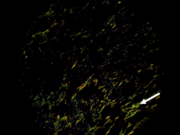

Carcinoma adenoide quístico. Colágeno Tipo I (flecha). Picrosirius red. Microscopía de polarización

Se observaron con microscopio NIKON ECLIPSE LV 100POL, para diferenciar colágeno tipo I (birrefringencia naranja amarillenta a naranja y rojo) de colágeno tipo III (birrefringencia verde o amarillo verdoso) en el estroma neoplásico.

Los resultados muestran un perfil de birrefringencia diferente en las fibras colagenas del estroma de los tumores benignos y malignos analizados.

En el estroma de los tumores malignos se observo un predominio de colágeno tipo I, en comparación con el tumor benigno investigado, con predominio de colágeno III.